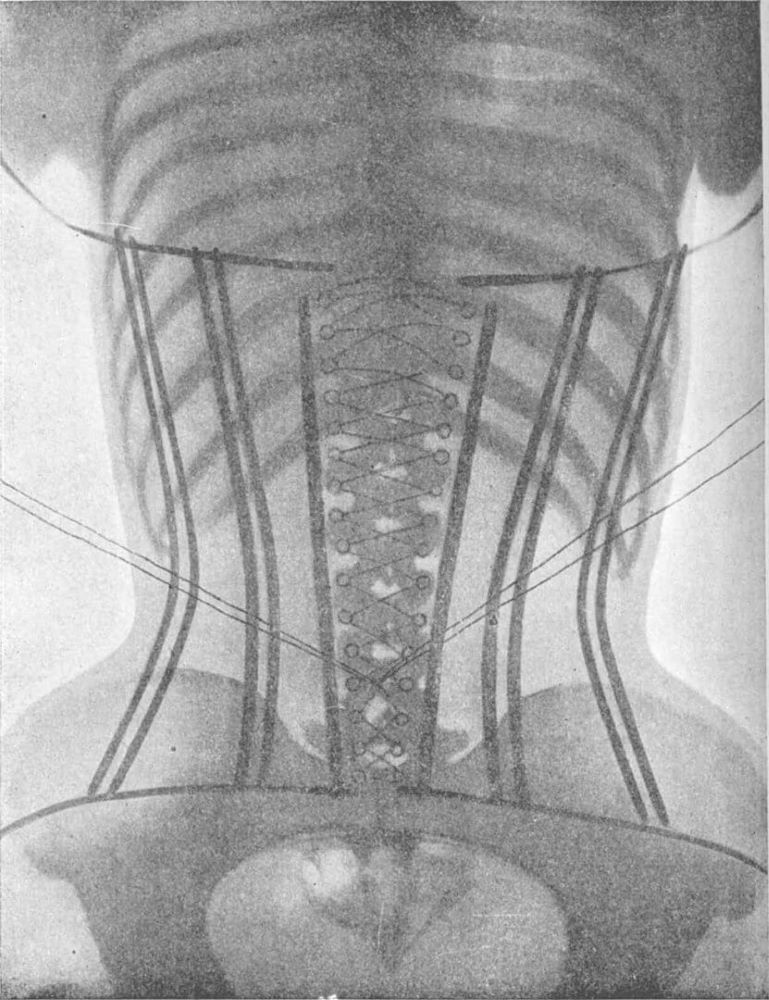

Moving Internal Organs

A corset can cause some shifting of internal organs and fat. However, when it is removed, the organs just go back to their normal positions, sort of like squishing a water balloon. Mainly, corsets lift the bust and squish the fat either down or up. It should also be kept in mind that internal organs are displaced during pregnancy, only to return to their original positions after birth.

When wearing a corset (or stays) there is some compression of the bottom of the ribs, making it harder to take a deep breath. However, you simply learn to breath more shallowly and in the top of your lungs. Honestly, after a few minutes of wearing a corset, I hardly notice I’m breathing differently.